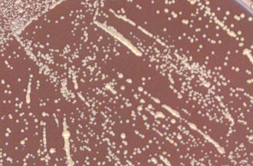

- Le réisolement à partir d'une colonie sur gélose au sang frais et celle au sang cuit donne l'aspect suivant après 48 h d'incubation à 37°C en aérobiose :